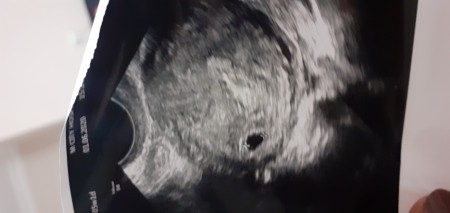

Kesede Bebek Ne Zaman Görülür

Kesede Bebek Ne Zaman Görülür.